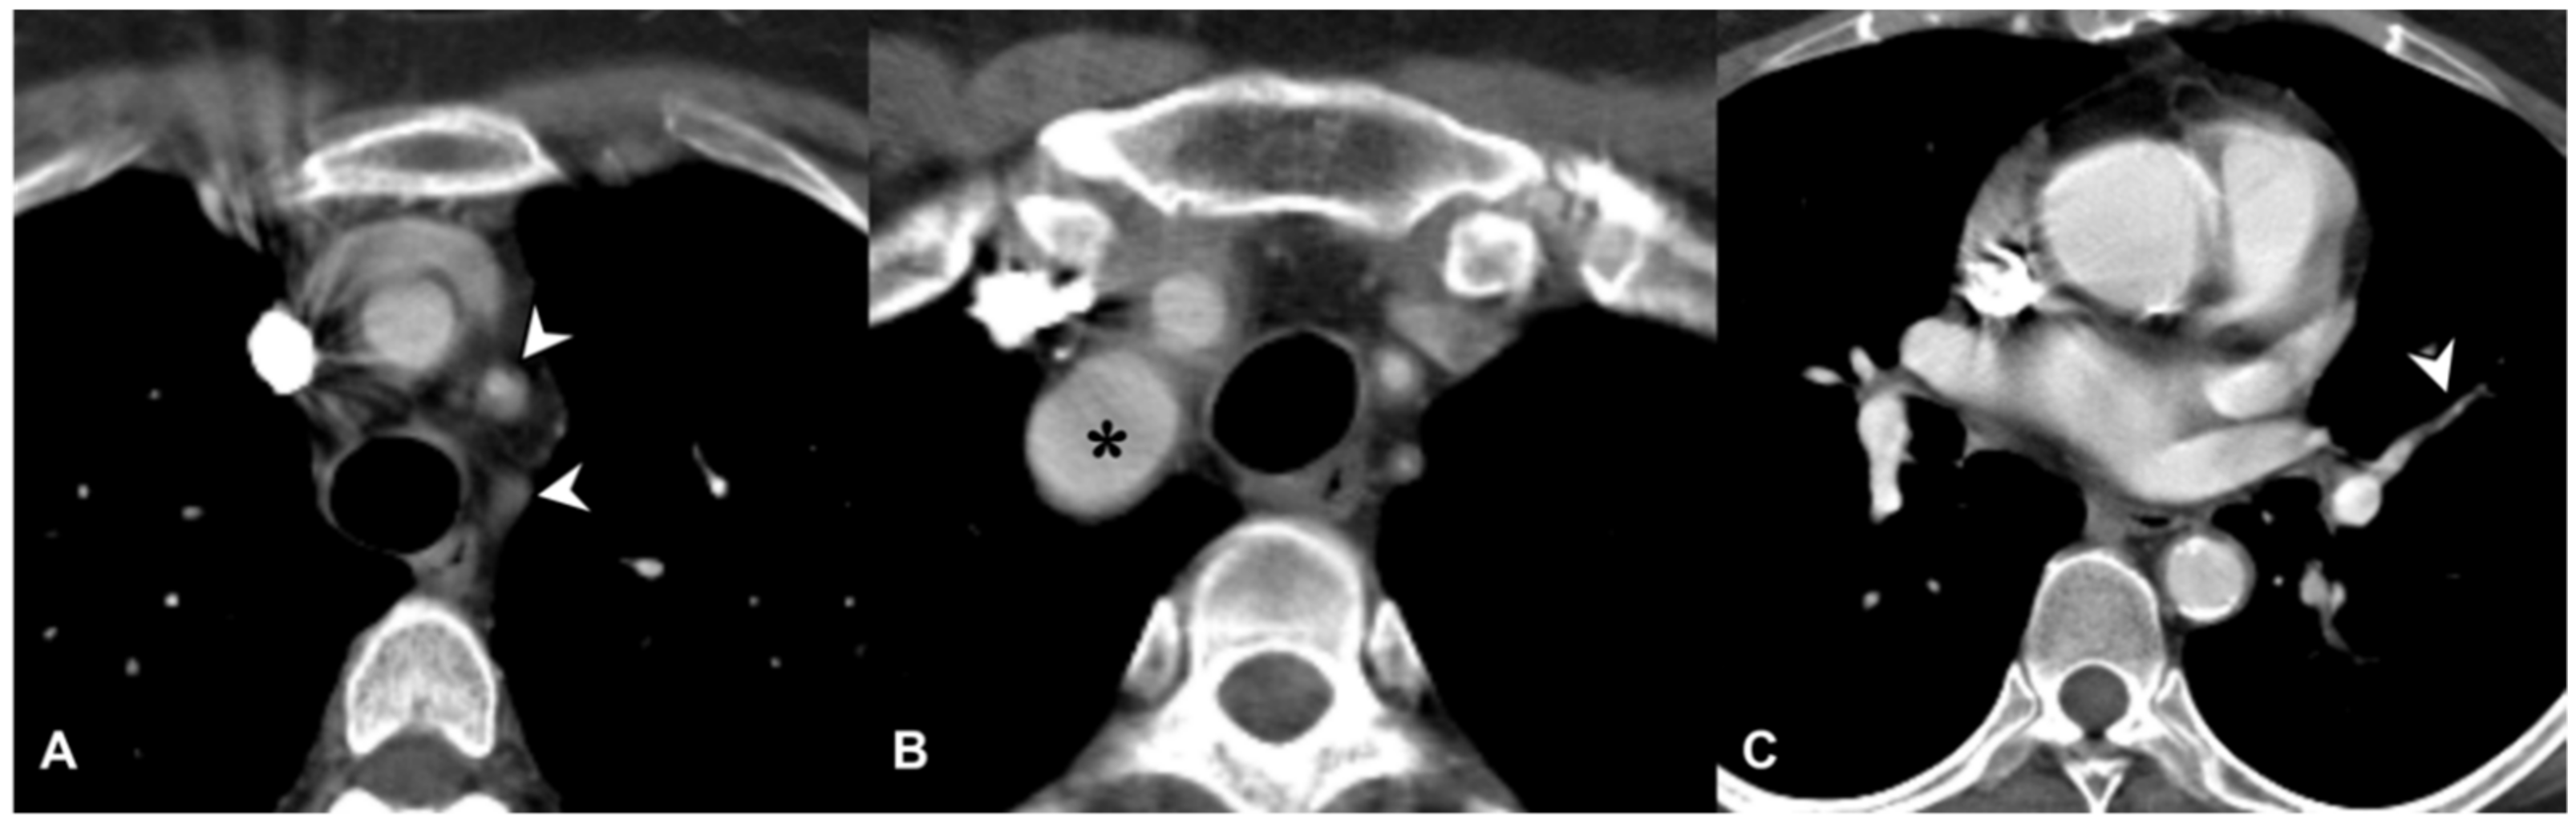

2.4. Granulomatosis with Polyangiitis (GPA-Wegener’s Disease)

2.6. Takayasu Arteritis (TA)

2.7. Giant-Cell Arteritis (GCA-Temporal Arteritis)